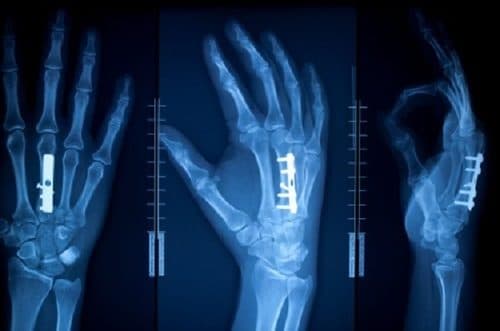

Chụp X quang giúp chẩn đoán xác định vị trí gãy xương và mức độ tổn thương

Phương pháp chụp X-quang chẩn đoán gãy xương bàn tay:

Thông thường sẽ tiến hành chụp X-quang ở hai tư thế là tư thế thẳng và tư thế nghiêng để xem xét hết các góc độ gãy. Qua chụp X-quang xương bàn tay sẽ thấy được chi tiết về đường gãy, kiểu gãy, sự tổn thương mô mềm và hệ thống dây thần kinh cũng như dây chằng xung quanh vết gãy xương bàn tay giúp bác sĩ có thể dễ dàng áp dụng những phương pháp điều trị phù hợp.